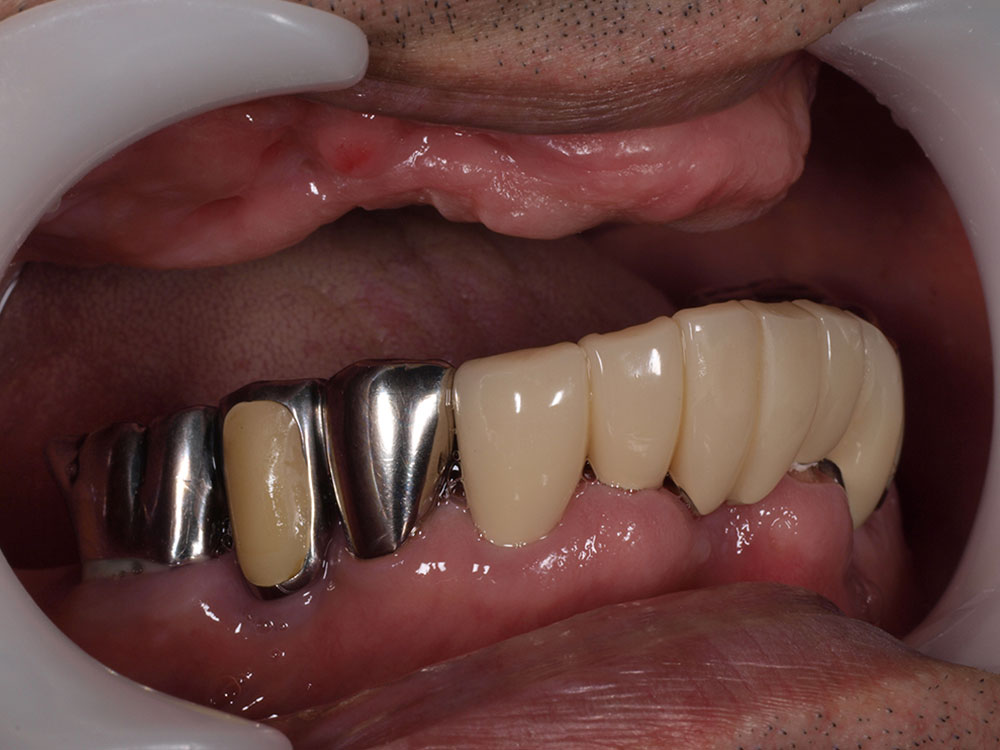

症例紹介

- 主訴

- 入れ歯が合わない。食べにくい。人生を豊かにしたい。

- 処置内容

- 上顎4本で12歯(オールオン4)、下顎4本5歯。

上下抜歯即時埋入、即時荷重(手術当日にインプラントの上に仮歯装着)

- 治療費用

- 上顎:約290万(税込)、下顎:約210万円(税込)

- 治療期間・通院回数

- 上顎:9か月/9回

下顎:6か月/7回

- リスク

- 術後の腫れ、痛み(ピークは3日後、1週間で軽減)

上部構造物、仮歯の破折、人工歯根脱落リスクがあります